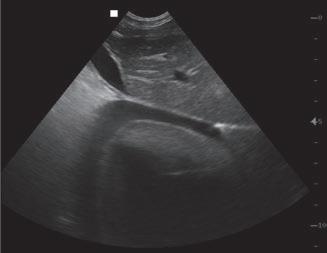

Diagnóstico ecográfico del derrame pleural canino y felino en urgencias

Las técnicas de radiología intervencionista permiten diagnosticar y solucionar patologías con una menor agresión tisular que otras cirugías invasivas y con una rápida recuperación. Son procedimientos sin dolor, rápidos y seguros, y una alternativa terapéutica cuando no es posible intervenir de forma convencional.

La radiología intervencionista es una especialidad que se encarga del diagnóstico y tratamiento de una gran cantidad de patologías de una forma mínimamente invasiva. Para realizar estos procedimientos es imprescindible disponer del equipamiento adecuado, tener nociones tanto de la instrumentalización como de las diferentes técnicas, y conocer con precisión la anatomía del paciente. Se trata de técnicas cada vez más implementadas en la clínica diaria ya que permiten solucionar diferentes patologías con una menor agresión a nivel tisular, una rápida recuperación, son procedimientos sin dolor, rápidos y seguros, suponen un menor coste respecto a otras cirugías invasivas, y constituyen una alternativa terapéutica a pacientes que no se pueden operar de forma convencional. Entre las más frecuentes destaca el cierre del conducto arterioso persistente, valvuloplastias en estenosis pulmonar, oclusión de shunts portosistémicos, implantación de marcapasos y colocación de stents

La radiología intervencionista se realiza mediante un abordaje guiado por distintas técnicas de imagen como, por ejemplo, la ecografía, la fluoroscopia o la tomografía computarizada, para alcanzar la zona a diagnosticar o tratar.

La radiología intervencionista, también conocida como radiología vascular e intervencionista, es una especialidad que se encarga del diagnóstico y tratamiento de una gran cantidad de enfermedades de una manera mínimamente invasiva. Se realiza mediante un abordaje guiado por distintas técnicas de imagen como, por ejemplo, la ecografía, la fluoroscopia o la tomografía computarizada, para alcanzar la zona a diagnosticar o tratar.